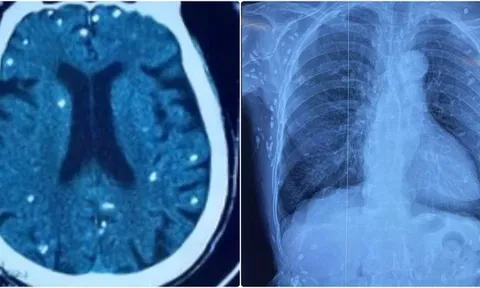

Theo bác sĩ Tuấn, việc ngừng thuốc sẽ khiến người bệnh đối mặt với nhiều hậu quả. Nghiên cứu tổng hợp trên hàng chục nghìn bệnh nhân cho thấy, chỉ vài tuần sau khi tự ngưng thuốc, nguy cơ đột quỵ tăng gấp 3 lần, nguy cơ nhồi máu cơ tim tăng gấp đôi (Turnbull et al., Lancet 2020).

Khi huyết áp tăng vọt, mạch máu não có thể vỡ, gây liệt nửa người hoặc tử vong. Áp lực cao kéo dài cũng làm tổn thương lớp nội mạc mạch máu, khiến mảng xơ vữa bong ra, gây tắc nghẽn động mạch vành, hậu quả là cơn nhồi máu cơ tim cấp. Trái tim phải làm việc quá sức, phì đại dần và cuối cùng suy yếu: theo Framingham Heart Study, tăng huyết áp chiếm tới 75% nguyên nhân suy tim ở người cao tuổi.

Đôi mắt có thể bị tổn thương bởi xuất huyết võng mạc, dẫn đến giảm thị lực, thậm chí mù lòa.